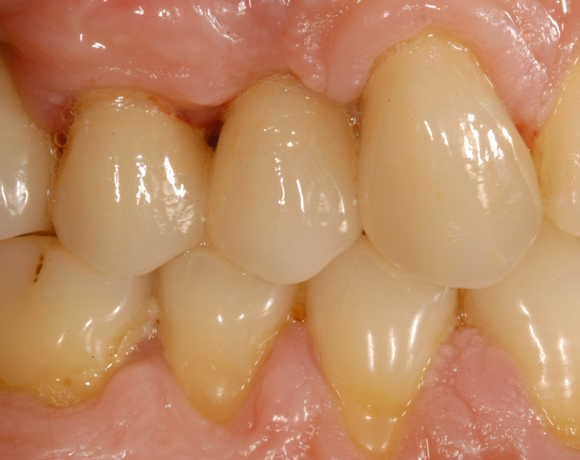

Bei dem letzten Patientenfall lagen Nichtanlagen der Zähne 12, 24, 34, 35, 44, 45 vor. Bei Zahn 12 schimmert das Implantat durch, es war sehr wenig Knochen vorhanden, aber das Ergebnis ist seit acht Jahren konstant gut. Zahn 22 lag als Zapfenzahn vor und wurde mit einem Veneer versorgt.